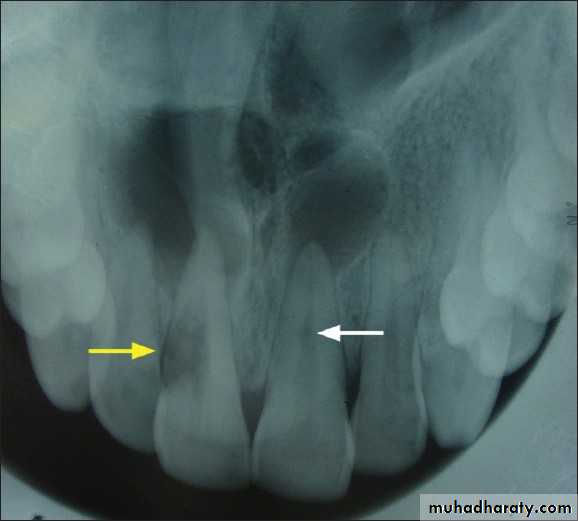

External root resorption

In external root resorption, root resorption affects the cementum or dentin of the root of tooth. It can be:

• Apical root resorption

• Lateral root resorption

• Cervical root resorption.

Etiology:

The same as internal root resorption but here it is mostly associated with trauma to the teeth that injure the cementum. Other factors include:• Infected necrotic pulp

• Over instrumentation during root canal treatment

• Trauma

• Granuloma/cyst applying excessive pressure on tooth root

• Replantation of teeth

• Adjacent impacted tooth.

Bleaching.

Radiographic Features

• Radiolucency at root and adjacent bone• Irregular shortening or thinning of root

• Loss of Lamina dura.